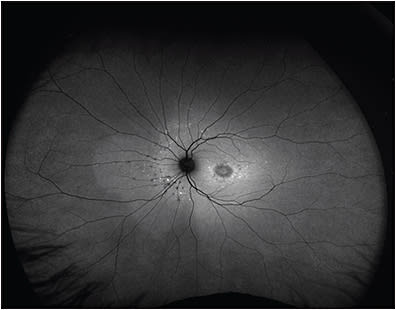

The peripheral retina manifests a variety of vitreoretinal disorders, including retinal vascular diseases, peripheral retinal degenerations, uveitis, retinal or choroidal tumors, and hereditary retinal dystrophies, among others.1,2 The gold standard for evaluation of the retinal periphery is a dilated fundus exam (DFE) with scleral depression performed by an experienced retina specialist. Recent technological advances in widefield (WF) and ultrawidefield (UWF) cameras have enabled unparalleled imaging of the retinal periphery, in contrast to older technology that captured about 30° to 50° of the posterior pole (Figure 1) and into the midperiphery with sweep views.3